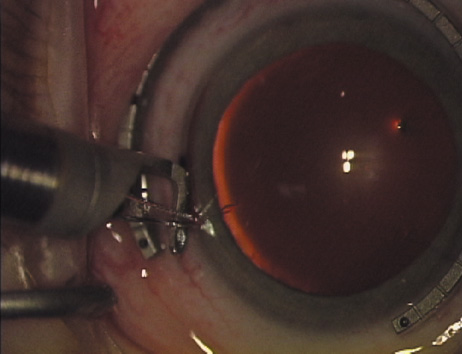

Case 1 is a 68-year-old male who presented for right cataract surgery. His refraction was −1.00 +2.25 × 80 and was recorded as reliable, consistent with his modest cataract density. Keratometry readings were 44.75 × 75 and 43.00 × 165. Corneal topography confirmed slightly more than 2.00 D of regular and slightly oblique cylinder. Consulting the nomogram, a plan was devised for a pair of LRIs to be centered over the 75-degree axis, with each incision delineating 45 degrees of arc. A single plane phaco incision was used and maintained at a size of less than 3.2 mm (Figs. 811).

Fig. 8. Steep meridian is confirmed intraoperatively by keratoscopy. In this left eye viewed from the temporal side, the “short axis” of the corneal mire is seen to be at the 75-degree meridian. (Reprinted from Hardten DR, Lindstrom RL, Davis EA. Phakic Intraocular Lenses: Principles and Practice. Thorofare, NJ: SLACK Incorporated, 2004, with permission.)